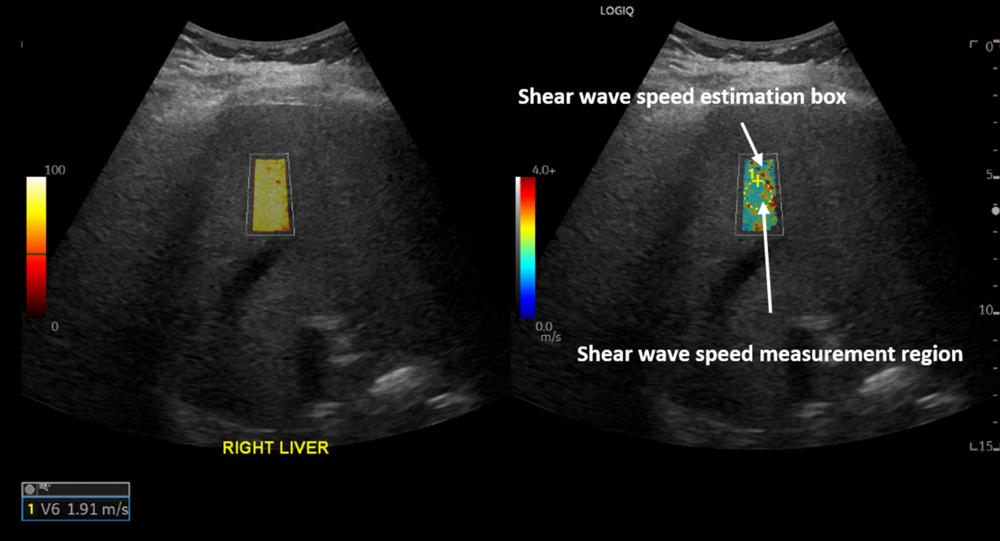

Figure 1. A 55-year-old female with a history of COVID-19 infection 38 weeks before the date of ultrasound shear wave elastography. The shear wave speed of 1.91 m/s corresponds to Young’s modulus of 10.94 kPa which indicates abnormally high liver stiffness and may reflect chronic liver injury.

High-res (TIF) version